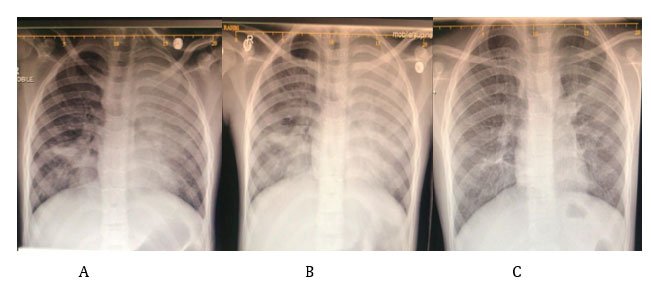

Mycoplasma pneumoniae in Children Beyond its Mild Presentation; A Case Report

Huda Al Habsi, Zakiya Al Rashdi and Hilal Al Hashami. 12(7): 69-72.